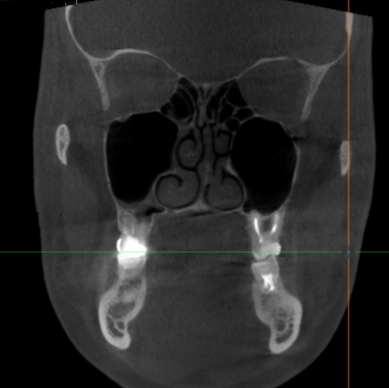

Обследование ЛОР Аноним 06/09/21 Пнд 14:02:46 #9 №1249743

image3A27741

Вопрос: какое наиболее информативное исследование можно представить отоларингологу при обращении за консультацией?

Раскрою тему: давно мучаюсь с левой стороной ЛОР. То ухо ноет месяцами, то тонзиллит, лимфоузел увеличен перманентно. С правой стороны все в порядке. Клуша в поликлинике разводит руками, экспериментирует на мне с разными препаратами, которые не помогают. Перепонка целая (смотрели на аппарате, похожем на инопланетный бластер). Направляли даже в областной НИИ, но мой визит к ним пришелся на здоровый период. Сказали, все ништяк, браток, гуляй! Намекнули на кривую перегородку (она кривая, да), но это выглядело, как отъебуха.

На днях поеду по работе в город, где есть корифей в этой области медицины. Много слышал про него и друг у него успешно лечился. Буду там всего пару дней, поэтому надо с порога дать исчерпывающую информацию. Времени на беготню по больницам там не будет. Да и консультация у него не дешёвая, чтоб по три раза ходить. Таки що мне уже ему показать: КТ, МРТ или они нахуй не нужны? Выручайте, посоны! Я плаванием занимаюсь, мне тренироваться надо с сентября. А после басика, бывает, ухо месяцами болит.

>>1249743

И кт и мрт. По этому он и будет судить о состоянии пазух.

Убедится, что в них норм, поставит хронический туботит и назначит гормоны в нос.